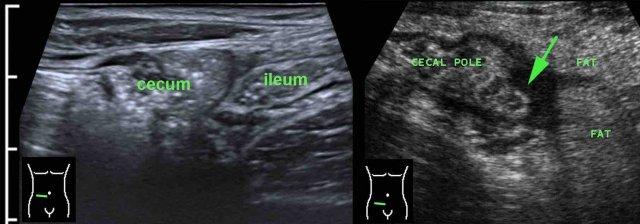

Trong viêm ruột thừa sau manh tràng (mũi tên), manh tràng thường bị đẩy về phía trong bởi đầu dò siêu âm, khiến ruột thừa (mũi tên) có vẻ nằm ở phía bên ngoài manh tràng thay vì phía sau nó.

Một khả năng khác để quan sát ruột thừa trong viêm ruột thừa sau manh tràng là đặt đầu dò ở vùng hông phải, nhờ đó tránh được manh tràng chứa đầy hơi và phân.

Một mẹo khác trong viêm ruột thừa sau manh tràng là dùng tay trái đẩy ruột thừa đang viêm (mũi tên) về phía đầu dò.

Để tìm ruột thừa, trước tiên có thể hữu ích khi xác định van hồi manh tràng (xem thêm Siêu âm đường tiêu hóa: giải phẫu bình thường).

Gốc ruột thừa thường được tìm thấy cách đó 3 cm về phía đuôi, nơi nó xuất phát từ cực manh tràng ở mặt trong.